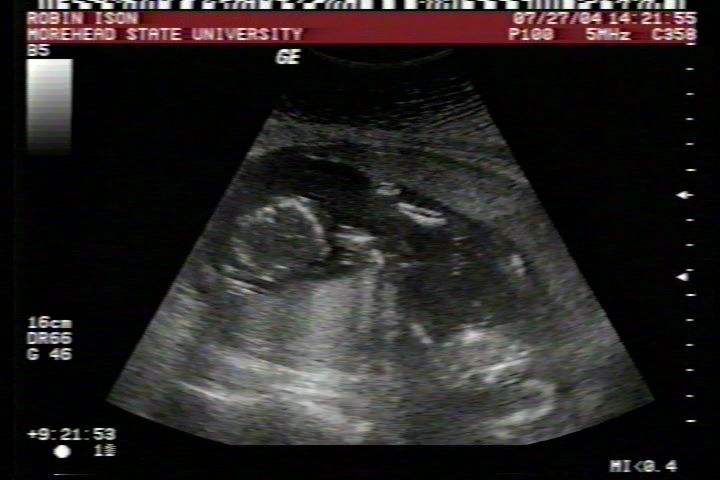

Pictures from Ultrasound at 17 weeks.